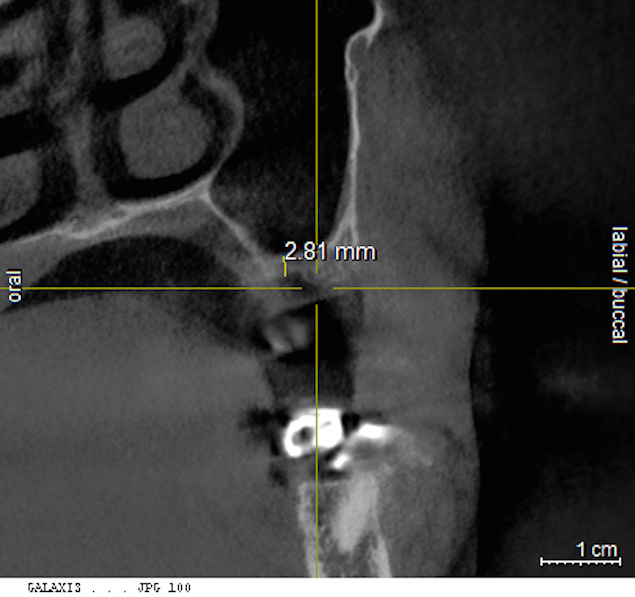

A patient who had received treatment 10 years ago for implants in the mandibular arch said her general dentist wanted to place an implant in site No. 3, using a hammer. Although that clinician believed the site had sufficient bone based on a periapical x-ray findings (Figure 21), the findings from a cross-sectional computed tomography scan helped determine that she had less than 3 mm of bone in the ridge (Figure 22). Froum et al14 and Tarnow et al15 both demonstrated the efficacy of combining rhBMP-2/ACS with mineralized bone allograft in sinus graft procedures. Marx et al16 demonstrated the combination of this growth factor with mineralized allograft and PRP to reconstruct severe maxillary defects. Given the 4 mm of minimal requirement for simultaneous implant placement, the author performed a lateral window sinus graft. An absorbable collagen sponge hydrated with rhBMP-2 was combined with mineralized bone allograft and used to obturate the site after reflection of the Schneiderian membrane along the medial sinus wall. A portion of the rhBMP-2/ACS was adapted over the grafted window osteotomy (Figure 23). After healing for approximately 5 months, the patient received a computer-guided implant surgery (Figure 24). The implant was restored with a screw-retained crown after a healing period of approximately 3 months.

Cross-sectional view of the edentulous site demonstrating minimal bone height below the sinus floor.

Figure 22